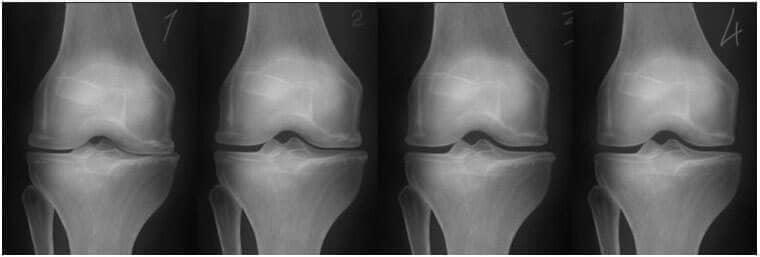

1. Nedostatek živin v kloubu. Dochází k narušení chrupavkové tkáně. 2. Obnovení chrupavkové tkáně v kloubu během 2 týdnů díky gel Depanten . 3. Obnovení chrupavkové tkáně v kloubu během 3 týdnů díky Depanten . 4. Zdravý kloub po dokončení kúry s gel Depanten .

— Na obrázku níže vidíte typický proces obnovy chrupavkového kloubu.